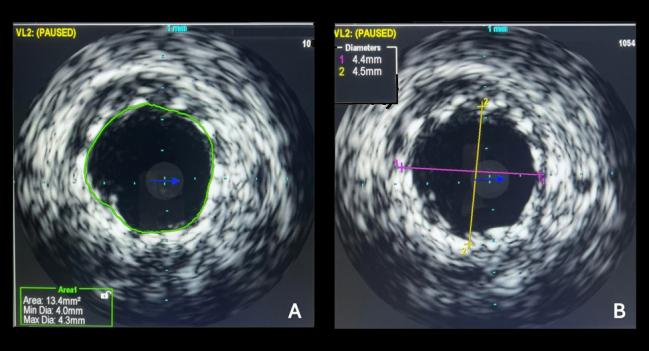

IVUS image after PCI for a bifurcation LM lesion showing the minimal stent area and the maximal stent diameter. Photo Credit: Ahmed Bendary

In this new study, investigators randomized 210 patients (mean age 62 years; 71.3% male) with left main coronary artery disease to PCI with IVUS or the control group without IVUS assessment. The lesion in the left main artery was located in the distal, midshaft, and ostial regions in 76.8%, 13.8%, and 9.4% of patients, respectively. Approximately 80% of patients had a SYNTAX score of 32 or less. There was no significant difference in baseline or lesion characteristics between study groups.

There was greater use of predilatation before stenting in the IVUS group than in the control group. Additionally, postdilatation balloon diameters, stent diameters, pressure for postdilatation, and procedural costs were all higher in the IVUS arm.